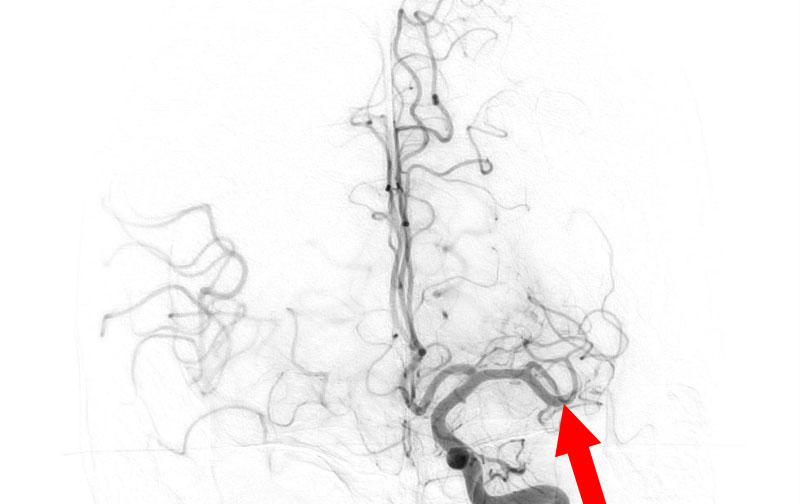

No.1481 手術前

No.1481 手術中

No.1481 手術後

脳動静脈奇形

20代

兵庫県の病院